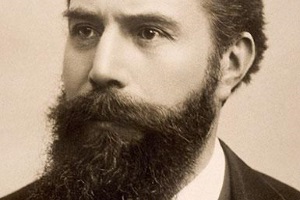

Вильгельм-Конрад Рентген – несомненно, одна из самых выдающихся фигур научного мира. Он обладал проницательным умом и изобретательностью, был даровитым и «тонким классическим физиком-экспериментатором».